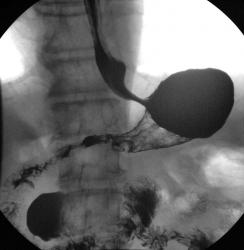

Пищевод.

Желудок

Случай.

дивертикулы пищевода

Изображение  Изображение